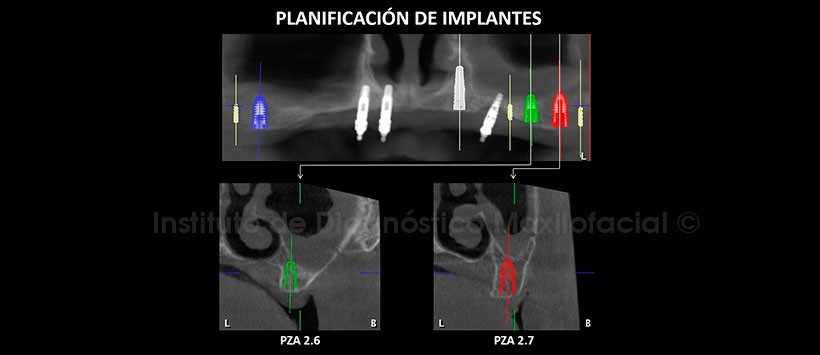

En la tomografía computarizada de haz cónico (TCHC), se realiza la planificación virtual de colocación de cuatro implantes dentales en zonas de piezas 17, 23, 26 y 27 (Figura 2, 3), y sobre la planificación se realiza la confección virtual de la guía quirúrgica (Figura 4). En la reconstrucción 3D (Figuras 5) se aprecia con detalle la orientación y la disposición final de los implantes dentales a ser colocados, además se observa la guía quirúrgica confeccionada virtualmente que posteriormente fue impresa físicamente para su utilización en el procedimiento quirúrgico (Figura 6).